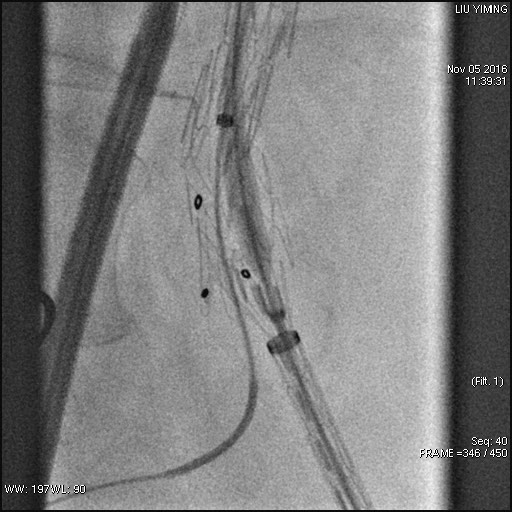

其中,在复杂主动脉病变腔内修复术应用手术直播中,郭伟教授带领其团队使用彩神在线网信彩票-彩神通免费版下载-彩神8争霸vlll-彩神购彩购彩大厅-彩神软件陆立根免费版-彩神ll争霸3-彩神ll彩神8-彩神ll争霸彩票-拼搏在线彩神网网页版科技公司的髂动脉分叉支架系统(IBD)以完全腔内重建的方式成功修复复杂腹主动脉瘤及髂动脉瘤。该例手术患者为64岁的男性,被诊断为肾下腹主动脉瘤,瘤体最大直径约6.5cm,双侧髂动脉瘤。患者成功植入彩神在线网信彩票-彩神通免费版下载-彩神8争霸vlll-彩神购彩购彩大厅-彩神软件陆立根免费版-彩神ll争霸3-彩神ll彩神8-彩神ll争霸彩票-拼搏在线彩神网网页版科技IBD支架,定位准确,无内漏,成功保留了左侧髂内动脉,术后造影显示髂内动脉通畅。

图:术前造影、术中造影、术后造影